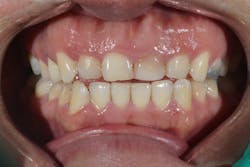

Figure 12: Pre-op clinical photo shows the discrepancies and disharmony of the gingival height. Incisions for esthetic crown lengthening on tooth No. 9 were done via the Er:YAG laser in contact mode (20 pps/60 mJ) to remove excess soft tissue in accordance with the pre-op probing depth measurements.

For soft-tissue procedures, similar to the CO2 laser, its clinical applications include incision, excision, vaporization, ablation, and coagulation of oral soft tissues, including excisional and incisional biopsies. Gingivoplasty, gingival depigmentation, removal of subgingival calculus in periodontal pockets, and sulcular debridement are also treatment modalities for this laser. Its unique attraction to its targeted chromophore allows this laser to ablate both tissues simply by adjusting the pulses per second and millijoules from the unit control panel.

Figure 16: Two-year post-op shows gingival health and maintenance of gingival tissues.

The Er:YAG laser has been more recently known for its ability to remove calculus from a titanium implant surface as well as detoxification (figures 17–21).9 Many authors have shown the laser’s use in combination with mechanical debridement to be superior when using a regenerative approach to treat peri-implant diseases (figures 22–26).10 A particular feature of this laser is the microexplosions that occur when the laser energy is absorbed by water. The volume of these explosions suddenly expand up to 1,000 times, covering more surface area of a titanium implant. It has been found that both contaminated debris and the contaminated oxide layer are removed as a result of these microexplosions.11